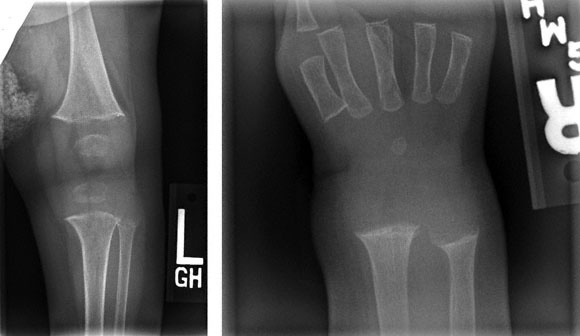

An 8-month-old boy is brought to the physician because his parents are concerned about his development. They report that he had learned to stand with support at the age of 4 months but has been unable to stand with or without support during the past 2 weeks. During this period, he has cried when held around his chest. His parents add that he has not grown much during the past 2 months. He was born at term following an uncomplicated pregnancy and delivery. He receives no medications. His diet consists of breast milk, rice cereal, and pureed fruits. His family lives in a cold climate. At his last examination 2 months ago, he was at the 25th percentile for length and weight. Today, he is at the 3rd percentile for length and 10th percentile for weight. He is alert and mildly irritable. Vital signs are within normal limits. Examination shows a dark complexion. Cardiopulmonary examination shows no abnormalities. The abdomen is soft. The wrists are widened and tender. He screams when picked up and when placed in a standing position. X-rays of the right wrist and left knee are shown. Which of the following is the most likely diagnosis?